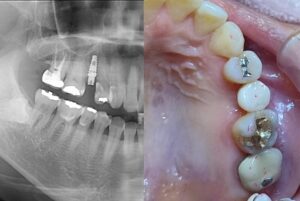

インプラント

インプラント治療

この症例を見る